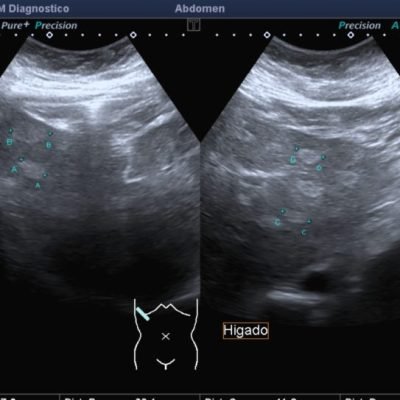

El médico de referencia le indica nueva ecografía de control, donde se observan múltiples y extensas lesiones focales hepáticas hiperecogénicas, redondeadas y confluentes, las cuales predominan en adyacencia a venas supra hepáticas, sin condicionar efecto de masa y sin alteración de la superficie hepática(fig. 1 y 2). Ante la valoración con Doppler color no presenta patrón de flujo peri ni intralesional y respeta el calibre de las venas supra hepáticas(fig. 3 y 4). Dada las características ecográficas se sospecha esteatosis focal multinodular confluente como principal diagnóstico presuntivo, siendo los diagnósticos diferenciales patologías de naturaleza infecciosa, tumoral o metastásica.